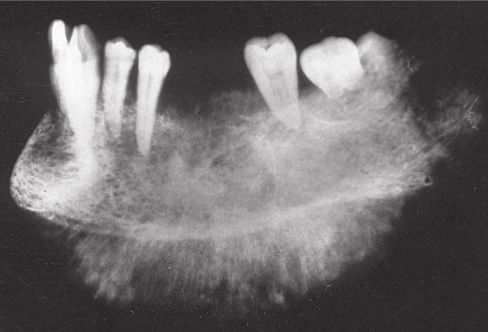

75.圖中 X 光影像最符合下列那種疾病? (A)纖維性發育不良(fibrous dysplasia) (B)慢性骨髓炎(chronic osteomyelitis) (C)惡性骨肉瘤(osteosarcoma) (D)蘭格罕氏細胞組織細胞增多症(Langerhans' cell histiocytosis)